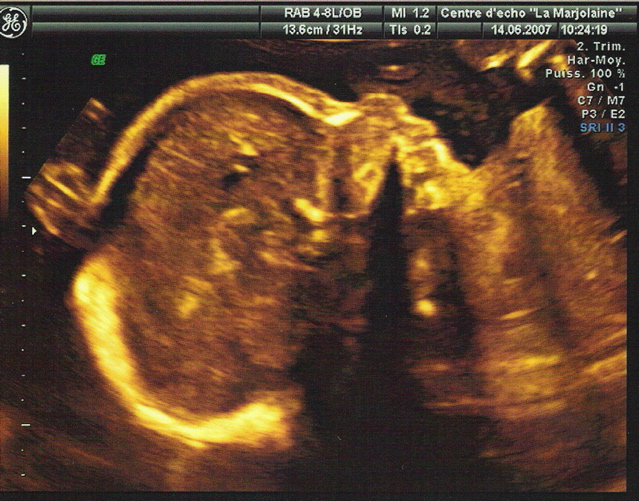

La deuxième échographie est formelle : ce sera une petite fille.

Elle va très bien et les augures prévoient un poids aux alentours de 3 kg au moment fatidique.